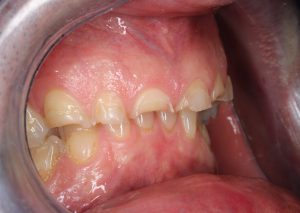

1.ábra: kiindulási kép szemből

A páciens erős bruxáló, a fogait pár milliméteresre csikorgatta. A szájvizsgálat és a panoráma röntgen alapján cariest, lágyrész-elváltozást nem találtunk, a páciens panaszait (folyamatos érzékenység hideg-meleg ingerekre, savakra) a nagymértékben abradált fogazat okozta. A megsüllyedt harapási magasság és a 2-3 milliméteresre csikorgatott frontfogak miatt teljes szájrehabilitációt javasoltunk 28 darab full contour cirkónium koronával.

3., 4.ábra: kiindulási szituáció oldalról és szemből